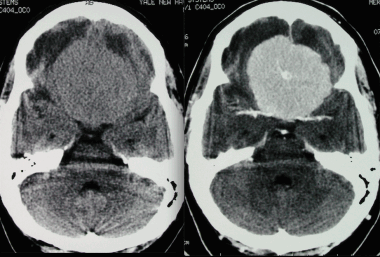

З адняя тенториальная менингиома на корональном КТ-изображении с контрастным усилением. К намету мозжечка прилежит объемное образование повышенной плотности с четкими краями. Визуализируются застой спинно-мозговой жидкости, легкий отек прилежащих тканей, гомогенный характер контрастирования, а также расширение желудочков.

Примерно 90% менингиом видны на КТ-изображениях. Основная роль КТ, по сравнению с МРТ, заключается в отображении изменений в подлежащих костях и наличия кальцинатов в опухоли.